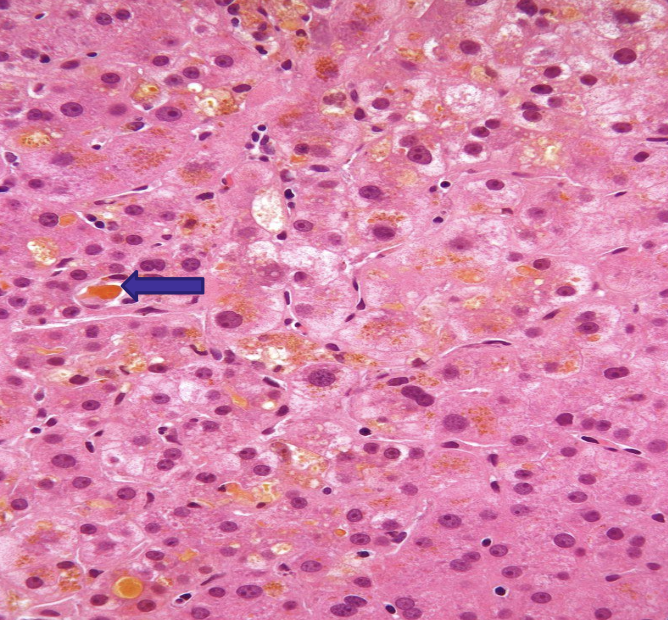

what does the image show?

canine copper-associated hepatopathy

copper accumulation